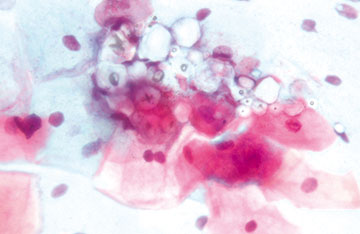

Bild 3

Alter der Patientin: 45 Jahre

Klinischer Befund: Zustand nach Ovarialkarzinom St. III

a. Endozervikales Adenokarzinom

b. Endozervikales Adenocarcinoma in situ

c. Metastase des bekannten Ovarialkarzinoms

d. Endometriumkarzinom